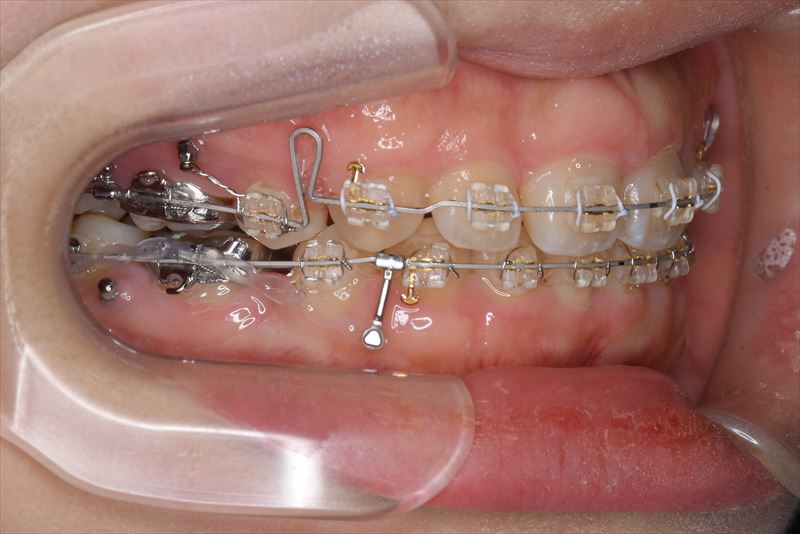

治療中

- 治療に用いた主な装置

- マルチブラケット装置、アンカースクリュー

- 上顎両側4番、下顎右側5番、下顎左側4番抜歯